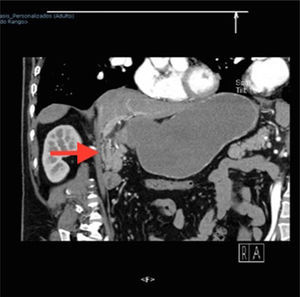

A 57-year-old man with an unremarkable past medical history complained of moderately intense localized pain in the epigastrium after eating solid foods, and later after drinking liquids. The accompanying nausea and vomiting caused important fluid and electrolyte imbalance, for which he was hospitalized. Laboratory tests and imaging studies were ordered and chronic cholecystitis with gallstones was diagnosed through ultrasound imaging (USG). A lesion infiltrating into the first portion of the duodenum and an ulcer were identified at endoscopy and at esophagogastroduodenography (EGD) (fig. 1). A computed axial tomography scan showed gas in the gallbladder and thickening of the gastric antrum and the duodenal bulb walls (figs. 2 and 3). Tumor markers were in the normal range. The patient underwent exploratory laparotomy that revealed chronic inflammation of the gall bladder, cholecystoduodenal fistula with loss of the normal anatomic arrangement, and annular pancreas (figs. 4 and 5) that did not compromise the integrity or permeability of the duodenum. Cholecystectomy was performed, the fistula was dismantled, and primary closure of the duodenum was carried out. The patient progressed favorably and is currently under follow-up at the hepatopancreaticobiliary surgery clinic.